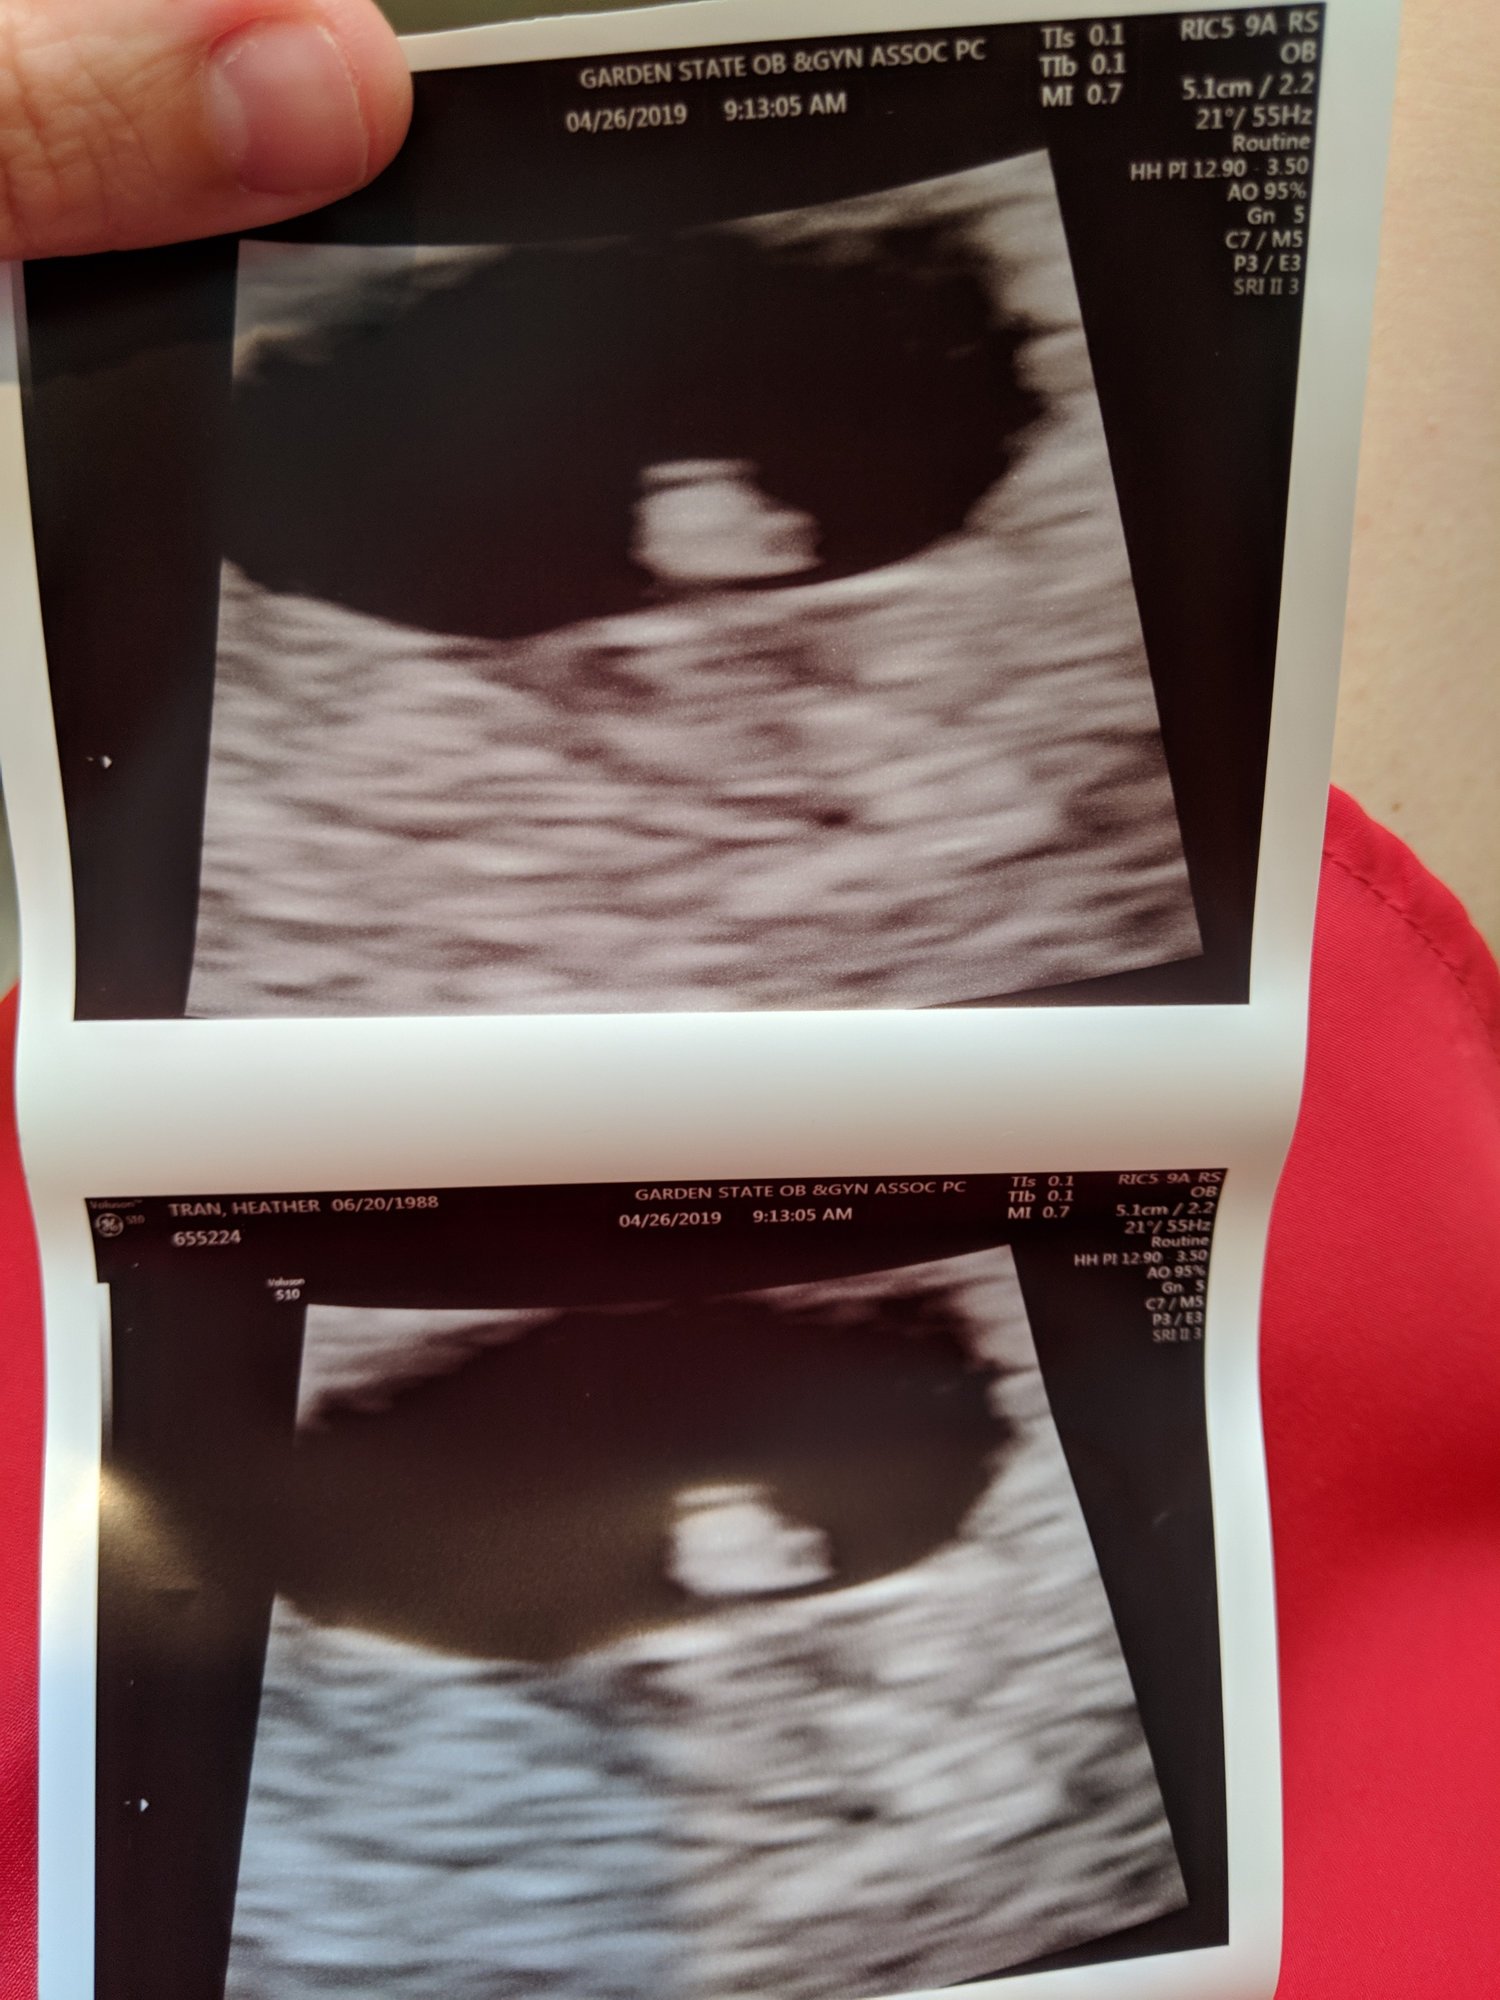

Not too much to see but there's a little baby there with a heartbeat of 122 BPM

The two black dots to the right are the hematoma bleeds😥 Pic was taken far away like this because they are more focused on the SCH.

Since I am very high risk i will be getting weekly ultrasounds to watch the bleed. Praying next week the baby will have grown and the hematoma will be smaller. Keeping faith.